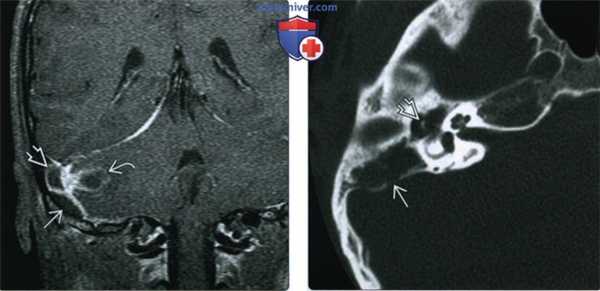

(Слева) При корональной МРТ Т1 ВИ С+ FS у этого же пациента ниже тромбированного сигмовидного синуса визуализируется эллипсовидный эпидуральный абсцесс. Виден и абсцесс в мозжечке; намет мозжечка накапливает контраст.

(Справа) При аксиальной КТ височной кости у этот же пациента определяется снижение пневматизации среднего уха и ячеек сосцевидного отростка, наряду с эрозией кортикального слоя сосцевидного отростка (сзади) и слуховых косточек, сопоставимой с отомастоидитом и холестеатомой, что и было подтверждено при операции.